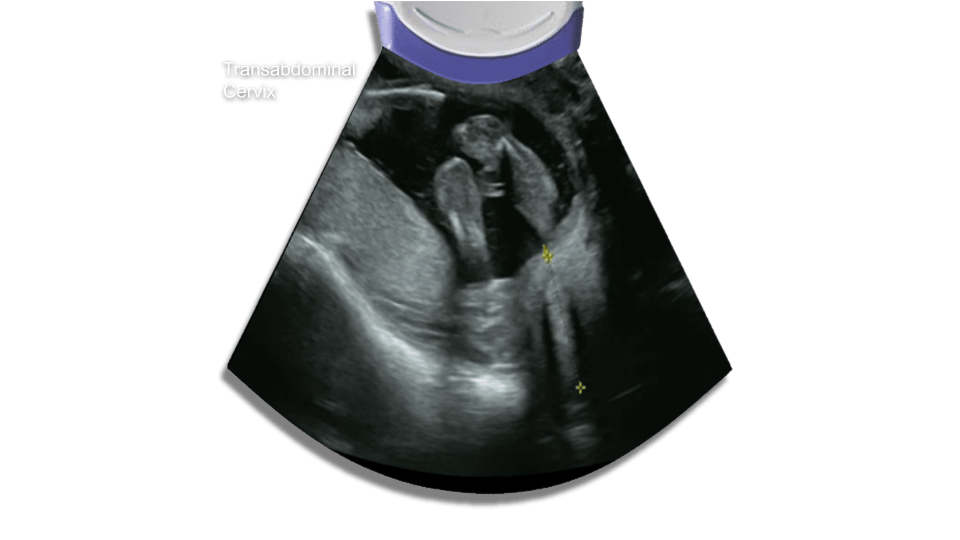

Cervix

The average length of the cervix is 3.5 cm. The cutoff usually used is 2.5 cm. If there is any cervical shortening or funneling (amniotic membranes bulging into the cervix) you may obtain a transvaginal ultrasound to confirm.

Potential pitfalls for transabominal approach:

Overfilled bladder masking cervical incompetence, also an underfilled bladder might make the cervix hard to image.